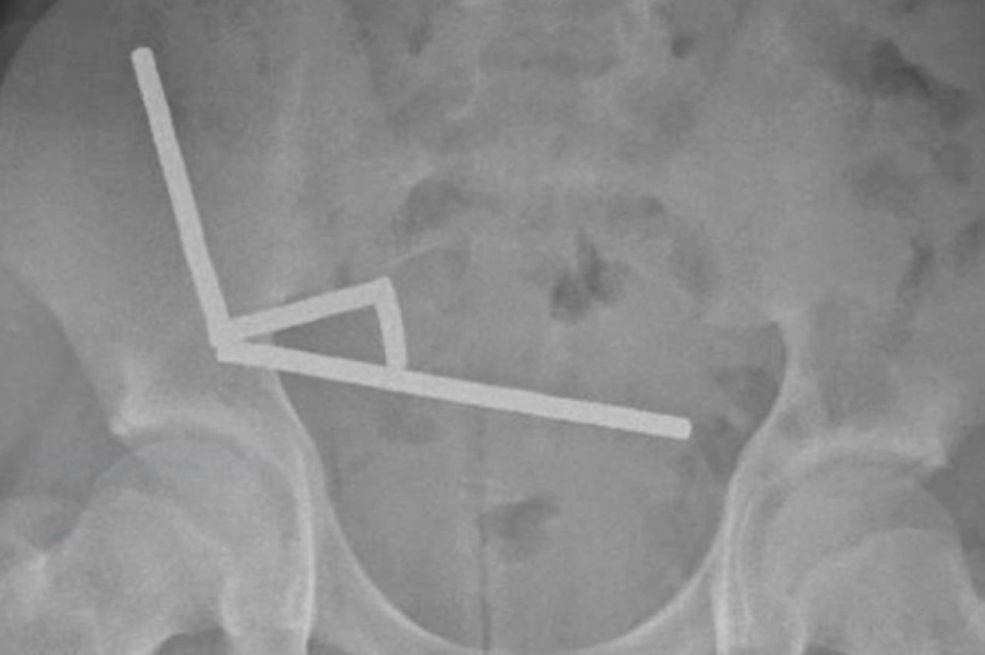

Rendgenske snimke otkrile su četiri linearna lanca magneta u različitim dijelovima dječakovih crijeva

Rendgenske snimke otkrile su četiri linearna lanca magneta u različitim dijelovima dječakovih crijeva. Nakon što su ušli u tijelo, magneti su se spojili.